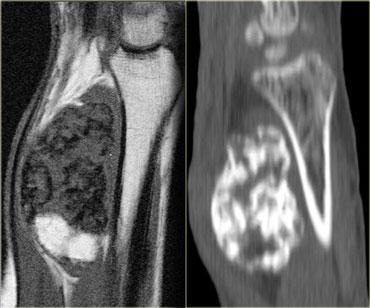

Myositis ossificans

Chấn thương đụng dập nặng gây ra khối máu tụ trong cơ có thể dẫn đến hiện tượng vôi hóa muộn trong mô mềm, được gọi là viêm cơ hóa xương.

Viêm cơ hóa xương có hình ảnh đa dạng tùy thuộc vào mức độ trưởng thành:

- Nonspecific mass

- Peripheral ossification

- Marrow cavity formation

Trên MRI, viêm cơ hóa xương có thể khó phân biệt với u xương ác tính (osteosarcoma).

Trên X-quang và CT, có thể thấy hình ảnh vôi hóa mô mềm không gắn liền với xương.

Bên trái là một trường hợp khác của viêm cơ hóa xương với sự hình thành xương.